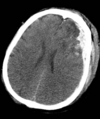

A 17 year old sustains a gunshot wound to the head. On examination, he has decorticate posturing on the right and he localizes on the left. His left pupil is 2 mm larger than the right but is still reactive. His non-contrast head CT (see figures) demonstrates metal and bone fragments within the left frontal region with an associated subdural hematoma with midline shift. What is the most appropriate management of this patient? Craniotomy, hematoma evacuation, superficial debridement Right frontal ventriculostomy placement Expectant care Craniotomy, hematoma evacuation, removal of all bone and metal fragments Superficial debridement of wound

The most appropriate management of this patient should include craniotomy, subdural hematoma evacuation, and superficial wound debridement. Gunshot wounds to the brain are often fatal and usually devastating. However, this patient's CT lacks significant negative prognostic factors, including bi-hemispheric injury, a bullet tract through the ventricles, or brainstem involvement. Neuroimaging does however reveal a space occupying acute subdural hematoma with midline shift. Thus hematoma evacuation might affect a significant improvement. The site of bullet entry should be superficially debrided but the literature suggests that aggressive debridement of the bullet tract offers no additional benefit unless containing an expansile hematoma. The patient is at significant risk of progression to brain death if the hematoma is not removed. Ventriculostomy does not ameliorate this situation. In this young, otherwise healthy patient with signs of cortical neurologic function, expectant management is inappropriate.